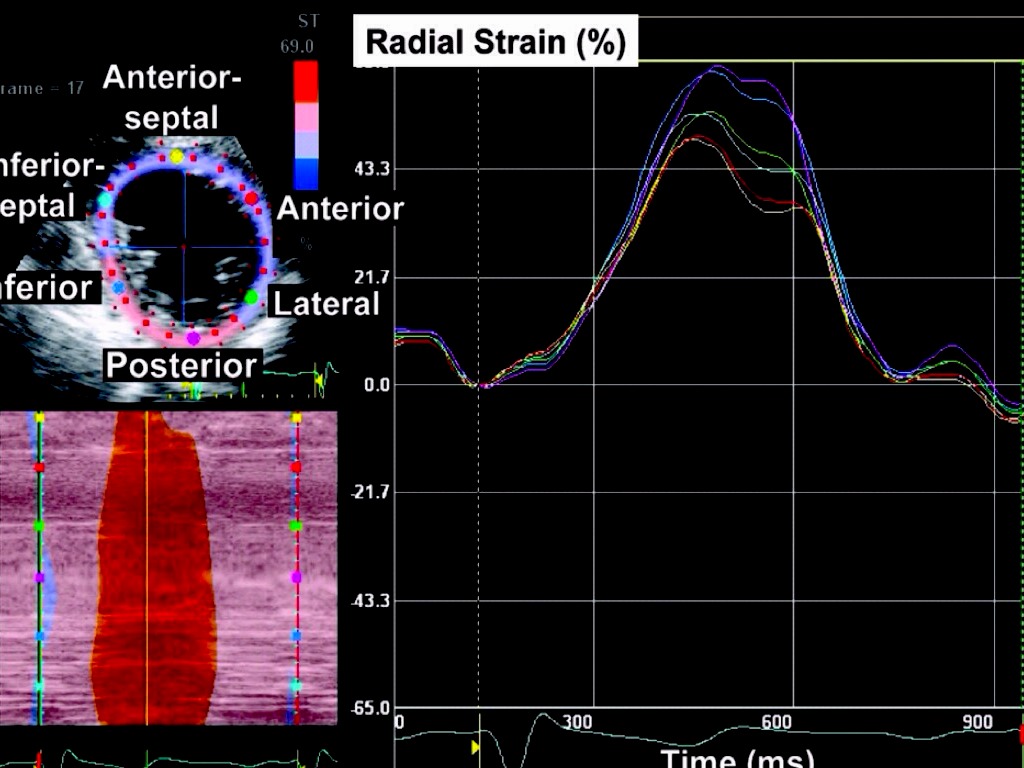

APLICAÇÃO DO STRAIN E STRAIN RATE NO DIAGNÓSTICO E MANEJO DA MIOCARDIOPATIA ISQUÊMICA

Georgia Rocha - MTDIC 4ª EDIÇÃO - Fev. 2014

Analise objetiva da deformação miocardica

Deteção precoce alterações contratilidade segmentar

Correlação com exames funcionais já estabelecidos na Cardiologia